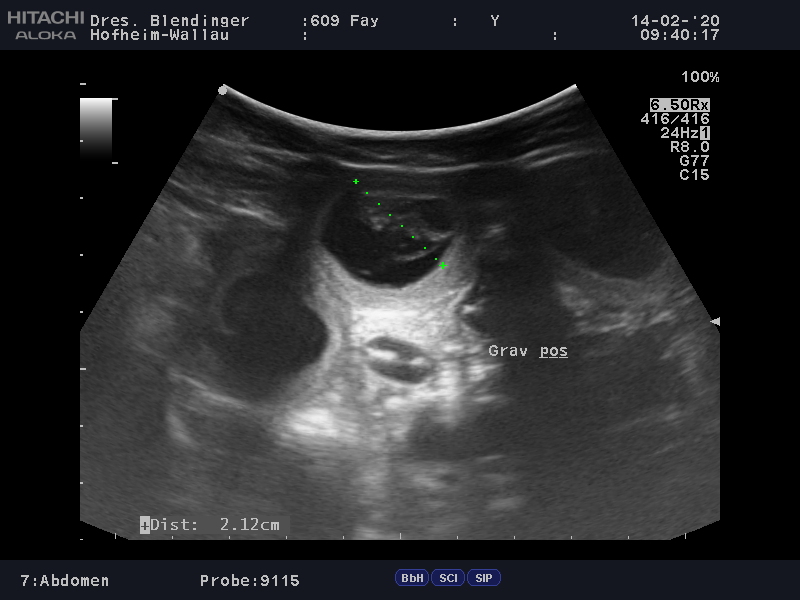

14.02.2020 - Ultraschalluntersuchung

Zu ihren 3.Geburtstag macht uns "Malimaniac's Faye"

ein sehr schönes Geburtstags,- Valentinstagsgeschenk...

"Faye" ist tragend nach "Eddie von Maliattack" und wir freuen uns riesig auf unseren I-Wurf.